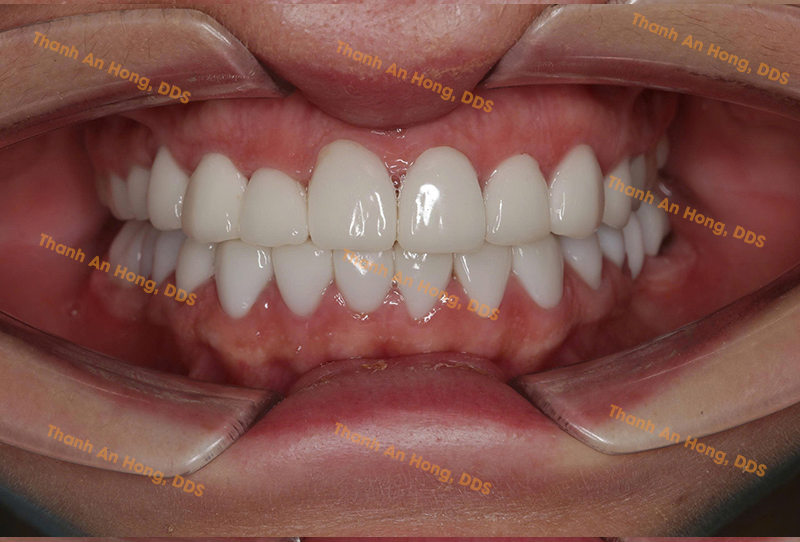

HÌNH ẢNH THỰC TẾ

Khay trong suốt chỉnh lệch đường giữa với toàn hàm là răng sứ